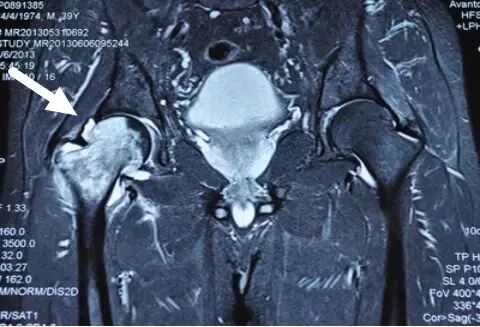

I期病人有髋部症状,X线片正常,磁共振出现异常

I期的患者在口服以上药物的同时,可以行股骨头坏死钻孔减压术,并且要定期复查,密切观察病情发展,尽量避免重体力劳动和爬山爬楼。